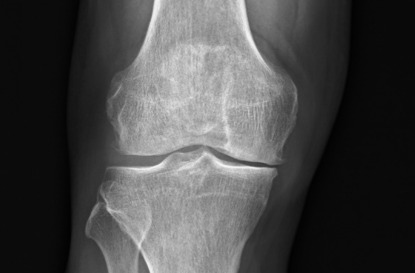

半膝人工關節置換術術前X光(膝蓋正面) -